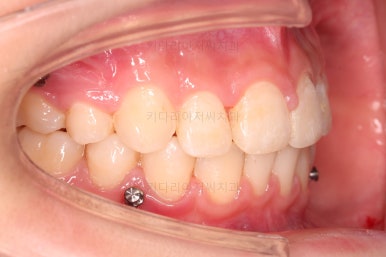

윗니는 틈을 점점 줄여가고요.

아랫니는 중간에 오히려 틈이 생기고 있죠?

이런 효과로 위아래 앞니는 급속도로 가까워지게 됩니다.

아랫니는 이후에 어금니를 앞으로 당겨오면서 빈공간을 줄여 나갑니다.

교합이 점점 맞아가네요.

윗니 뽑은 자리도 거의 다 줄었습니다.